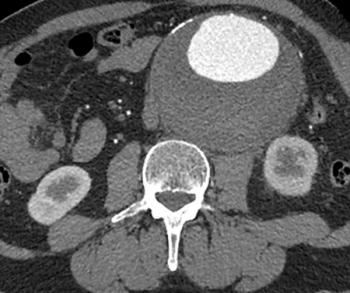

In a recent video interview, Kathy Schilling, M.D., discussed findings from a study of ProFound AI, an adjunctive artificial intelligence (AI) software for digital breast tomosynthesis (DBT), that demonstrated a 23 percent increase in breast cancer detection in comparison to DBT alone.